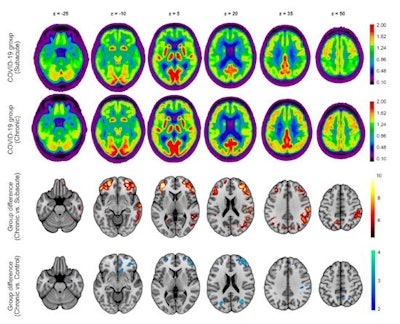

Group analysis using statistical parametric mapping revealed a widespread increase of F-18 FDG uptake in frontoparietal and, to a lesser extent, temporal neocortical regions in patients in the chronic stage compared to the subacute stage. No regions with significant decrease in glucose metabolism were identified. Voxel-wise comparison of chronic-stage patients to the age-matched control cohort confirmed the presence of a remaining neocortical hypometabolism in COVID-19 patients even at the chronic stage at an exploratory statistical threshold.

Performance on the MoCA test significantly improved over time, from a mean global score of 19.1 ± 4.5 (maximum 30 points) at the subacute stage to 23.4 ± 3.6 at the chronic stage; however, the scores were still below the frequently used cutoff value for detection of cognitive impairment (< 26/30), according to the authors. Five of eight patients were still below this threshold. MoCA scores showed that orientation and attention were almost unimpaired at the chronic stage, but they revealed persistent deficits in visuoconstructive and executive functions and, especially, memory.

However, in comparison to a control cohort, chronic COVID-19 patients still exhibited a slightly higher pattern of expression (at trend-level) and residual hypometabolism, which indicates a shift toward normal levels, but not a definite return, they said.